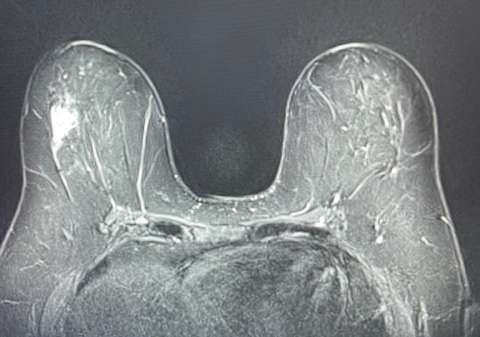

Case: Lymphoma of the Breast Figure 3

Axial STIR Blade demonstrates a focal nonmass enhancement that surrounds a biopsy clip at 9:00. Biopsy yielded a result of low-grade B-cell lymphoma.